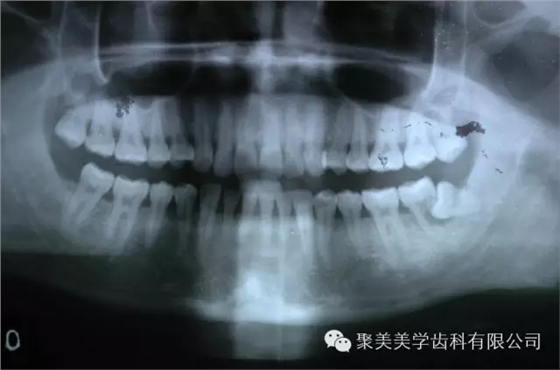

阻生牙把前面的牙齒頂壞了,兩個(gè)牙齒都需要拔除!

放大看!

被阻生牙頂壞的相鄰牙無法治療,只能拔除了,非??上?!

智齒本來就是多出來的牙齒,成年人一共有:28顆牙,上下各14顆,長出的4顆智齒屬于多余的牙齒,上面已經(jīng)講的很清楚,智齒對于人的身體的傷害,所以,如果長出來的智齒已經(jīng)影響了您的生活,請盡快到專業(yè)口腔診所拔掉吧。